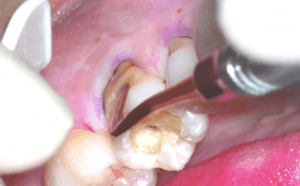

さて今日は金属の下で広がるむし歯治療についてです。

臨床を行っていると虫歯の再発による再治療を行うことが多いのです。特に金属のインレーを装着して何年か経つとインレーのきわと歯のエナメル質の間に隙間ができてくることがあります。その隙間は特に機能咬頭側のエナメル質がすり減り割れることで出来、そこから虫歯が再発することが多いように思います。

これは金属の硬さと歯のエナメル質の硬さに差があるため長年咬合力が加わることですり減るスピードが異なることで起こると考えています。

金属を除去してみると大きな虫歯が確認できました。

遠心方向からタービンなどの切削器具を用いる場合はミラーテクニックを併用します。特にエナメル質を保存する場合はアンダーカット部の軟化象牙質の除去にはエアースケーラーのラウンドチップを用いての除去が優れていて使いやすいと思います。